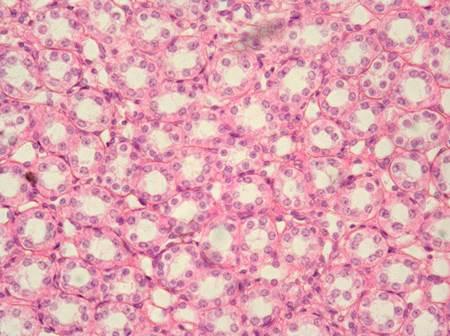

Name the tissue?

areolar

adipose

blood

bone

blood

Name the tissue

simple squamous

adipose

reticular

areolar

adipose